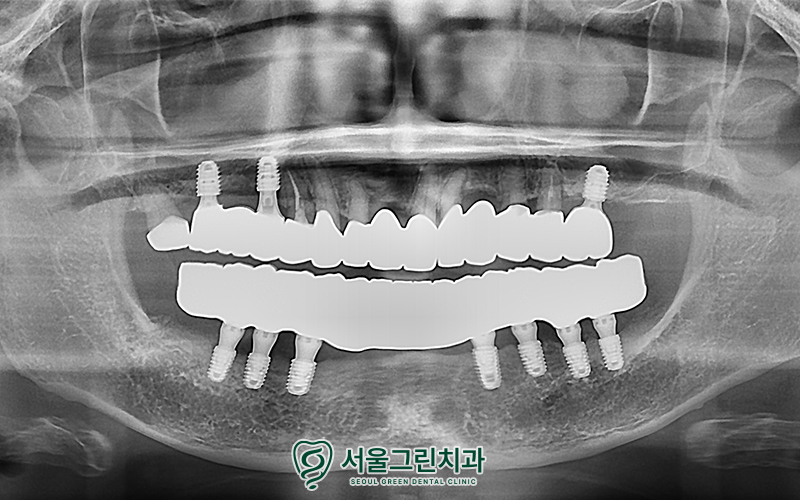

위아래 모든 치료가 마무리 된 후,

구강 내 모습입니다!

환자분의 연령, 구강 상태,

비용 부담까지 종합적으로 고려한

맞춤형 치료 계획을 통해

성공적인 치료결과를 보여드렸습니다.